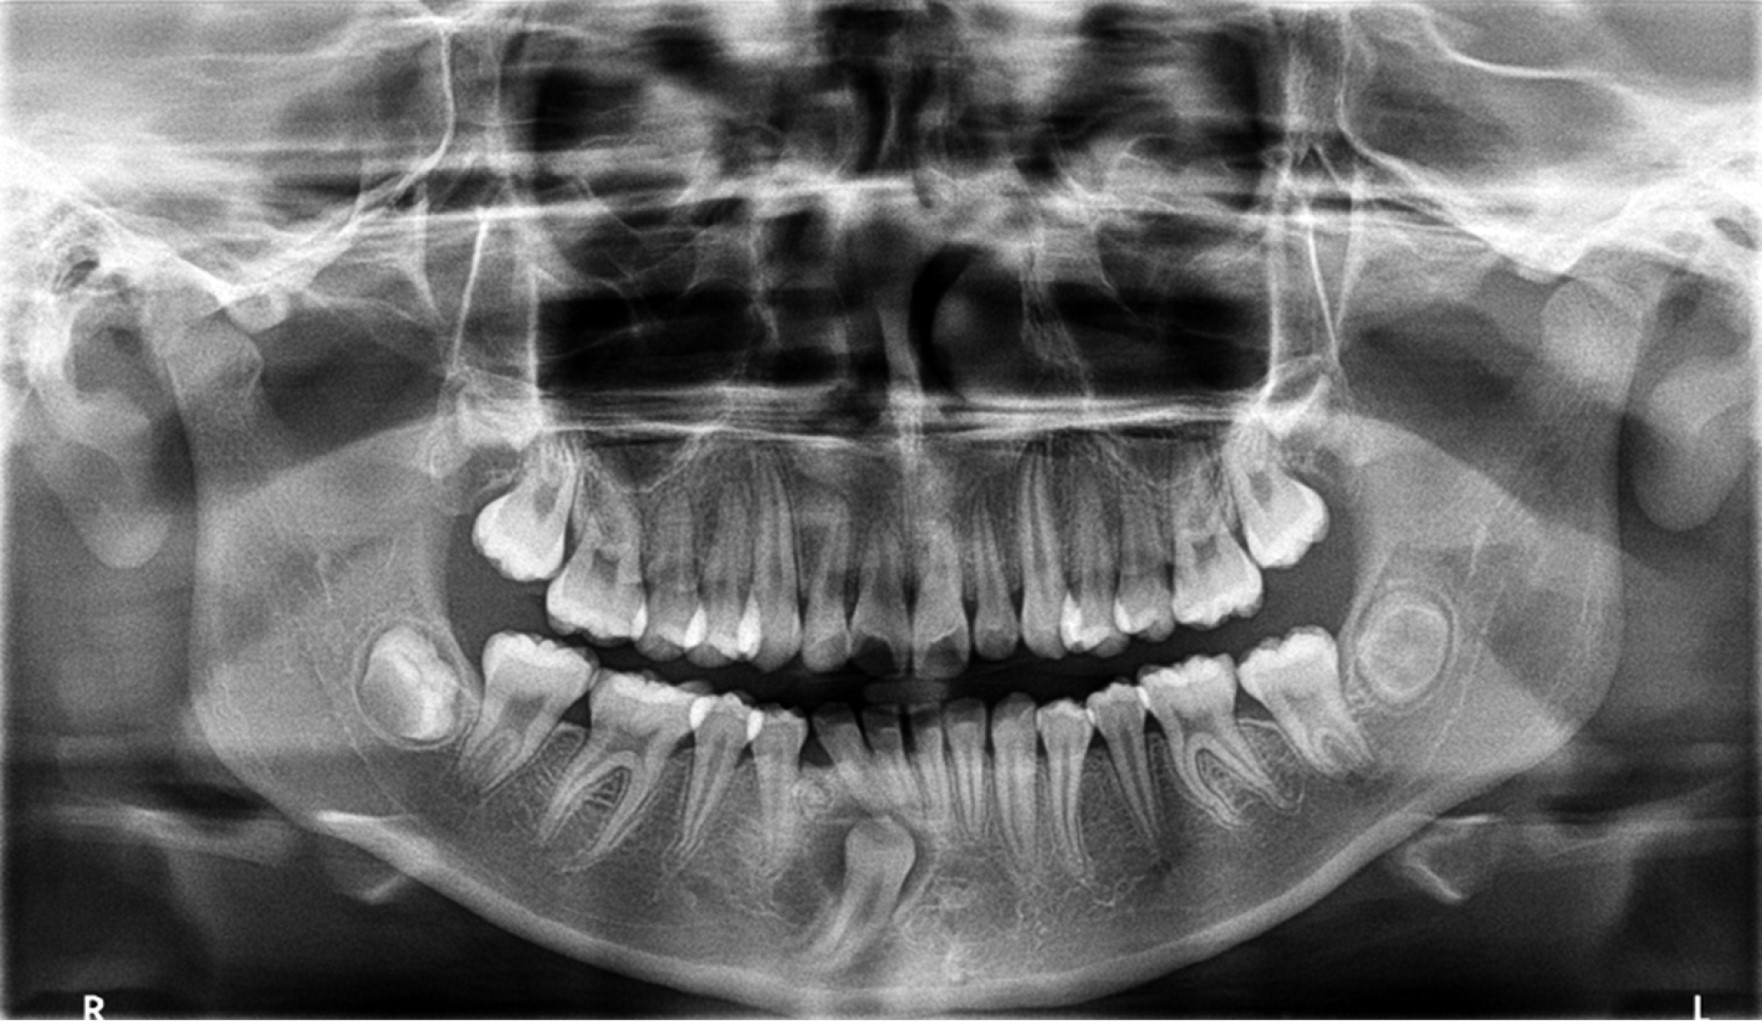

En la radiografía panorámica se observó una zona radiolúcida alrededor de la corona del órgano dentario 43, con márgenes bien delimitados que emergen de la unión amelocementaria, con medida aproximada de 15 mm de diámetro; también se identificó una imagen independiente a la anterior, la cual es mixta radiolúcida y radiopaca con bordes bien definidos, mesial al órgano dentario 44, a nivel de tercio medio radicular (Figura 1). La tomografía computarizada (TC) reveló que la cavidad quística rodeaba la corona del órgano dentario 43 (Figura 2). Por las características de los exámenes radiográficos, el diagnóstico presuntivo de la entidad alrededor de la corona del órgano dentario 43 fue un quiste dentígero, y el de la entidad mesial al 44 fue un odontoma. Se planificó una cirugía con el objetivo de realizar la escisión quirúrgica completa de ambas entidades y efectuar estudio histopatológico para corroborar su diagnóstico y, de ser posible, la colocación de un aditamento de ortodoncia en el órgano dentario 43 para su futura tracción y correcto posicionamiento en la arcada.

Figura 1